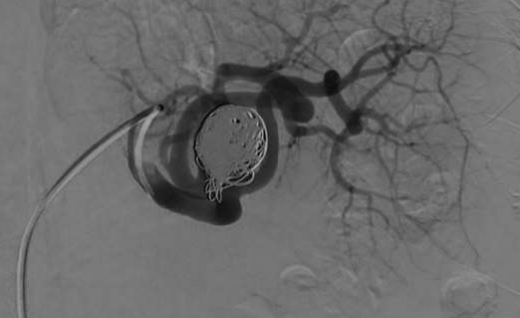

中年女性,间断左上腹部疼痛3个月,近期加重。CT显示10厘米的脾动脉瘤,近期动脉瘤内出血(瘤内血栓后再有血流入)。

腹腔造影证实为一个巨大的动脉瘤,脾动脉既是近端供血,也是流出道。导管成功进入流出道。

血管造影的另一个视图显示了脾动脉供体的造影剂喷射,以及对周围器官和血管造成肿块效应的动脉瘤的巨大尺寸。 |

腹腔血管造影的病人采取不同的投影,以更好的解剖可视化。血流入口(红色箭头)和流出口(黄色箭头)均暴露于脾动脉。在6Fr MachI作为引导导管的支持下,用5Fr 导管进入流出道,微导管经5F导管进一步进入流出道。

巨大脾动脉瘤是罕见的,并且由于其巨大的体积而难以栓塞。适用前后门栓塞的原则,但在如此大的动脉瘤中,后门插管是困难的。良好的支撑导管是关键。巨大的动脉瘤囊本身也被证明很难完全栓塞。可能需要不同栓塞剂的组合——在这种情况下是弹簧栓子/NBCA/凝血酶。以确保足够的流量进入这些巨大的动脉瘤。